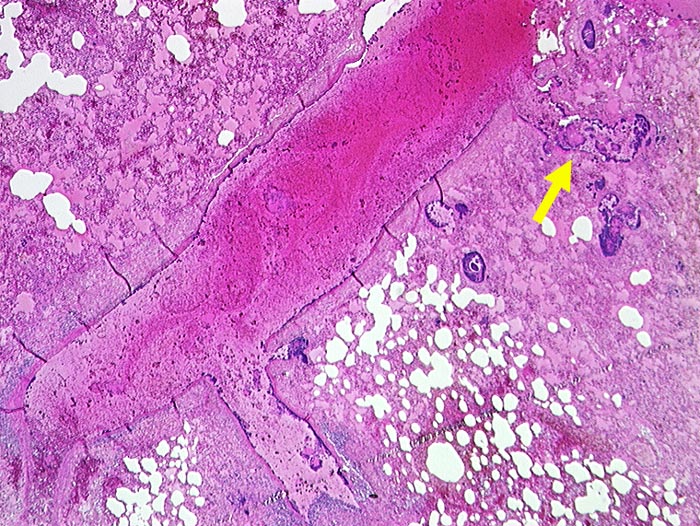

► Blaue Bakterienhaufen in einem Pulmonalarterienast und im angrenzenden Lungenparenchym. Lungenödem und Hämorrhagien.

Septische Embolien in der Lunge. Nachweis koagulasepositiver Staphylokokken im Blut und im Perikarderguss.